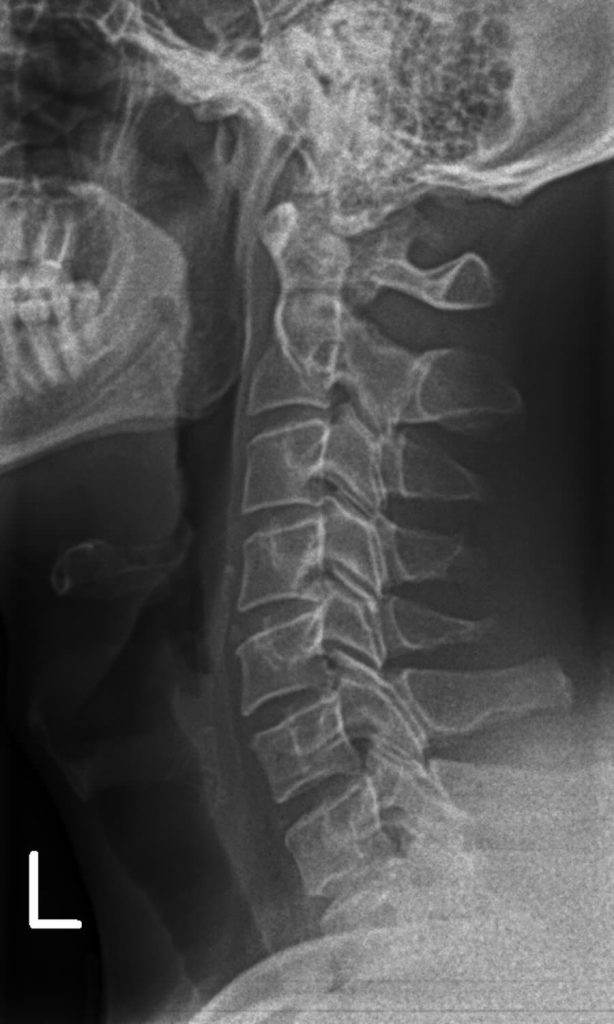

The two patients on the x-rays below would both appear very similar from a postural perspective just looking at them. But based on their neck x-ray curvatures, they would both require very different home exercises and traction devices. This is one of the reasons that a thorough assessment is so important.

Two people can look almost identical — same rounded shoulders, same forward head — yet have completely different structural patterns on their x-rays. One might need gentle thoracic extension work, while the other requires pelvic realignment first. The difference can often be invisible from the outside.